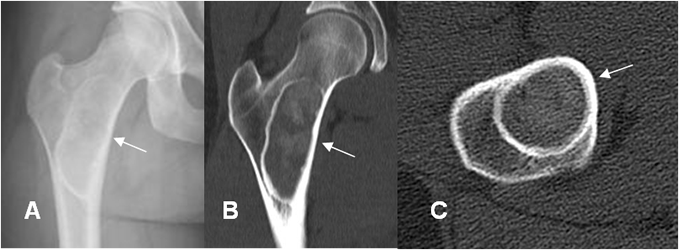

Fig 103 A. Displasia fibrosa.

A: Rx AP. Imagen ovalada, de bordes bien definidos y escleróticos, en el cuello femoral. No hay ruptura de la cortical, ni masa de tejidos blandos.

B: TAC reconstrucción coronal y C: TAC axial en ventana de hueso. Imagen de apariencia benigna, con matriz en “vidrio deslustrado”.